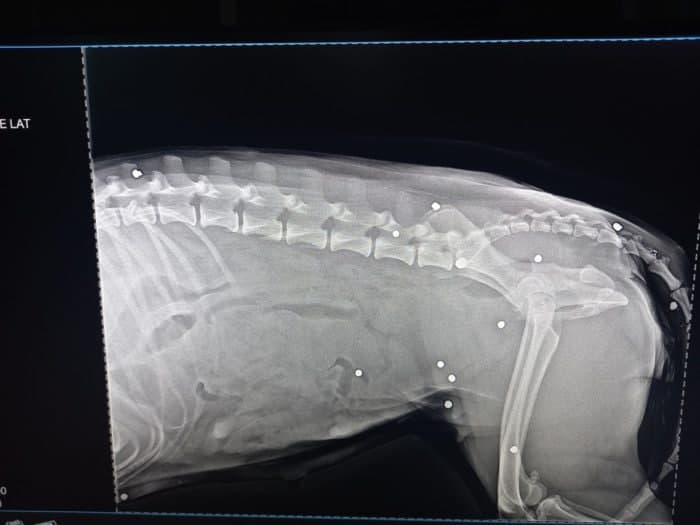

На собаке начитали 19 дробин в ходе проведенного регента.

Ранения были выявлены в брюшной полости, позвоночнике, голову, горло, глаз и грудь.